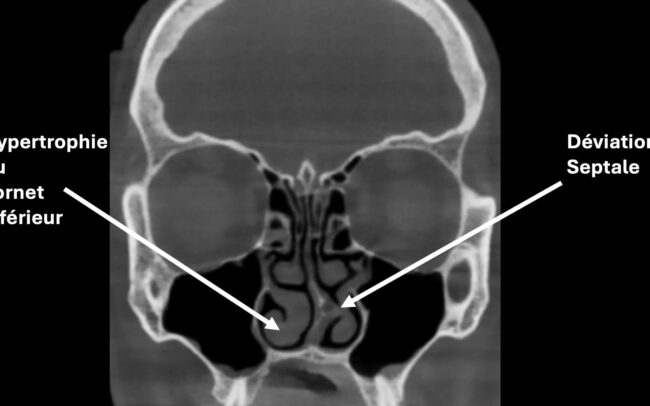

Cloison nasale déviée

Une déviation de la cloison nasale peut gêner la respiration, surtout d’un seul côté. Cette anomalie est souvent d’origine congénitale ou due à un traumatisme nasal.

Le traitement est chirurgical : il s’agit d’une septoplastie, qui permet de redresser la cloison

Hypertrophie des cornets

Les cornets sont des structures osseuses recouvertes de muqueuse qui peuvent augmenter de volume, notamment en cas d’allergies ou de sinusite chronique, rendant la respiration nasale difficile.

Les traitements sont les sprays nasaux à base de corticoïdes ou en cas d’échec du traitement médical, une réduction du volume des cornets par radiofréquence